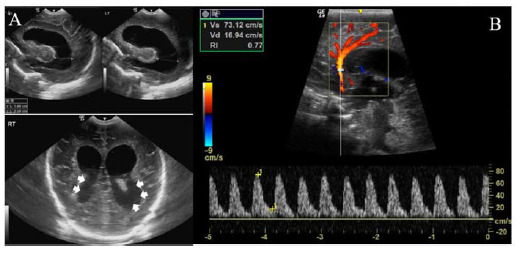

Case presentation: A set of preterm male triplets born at 30 weeks of gestation were admitted to the neonatal intensive care unit. At two weeks of age, the infants showed clinical manifestations of LOGBS sepsis, including septicemia. Additionally, one of the triplets developed meningitis complicated by hydrocephalus, while another developed necrotizing enterocolitis (NEC). Concurrently, their mother was diagnosed with mastitis and her breast milk cultures tested positive for GBS. The triplets were treated with systemic antibiotics. However, triplet B subsequently required a ventriculoperitoneal shunt for hydrocephalus management, and triplet C underwent laparotomy for NEC treatment.